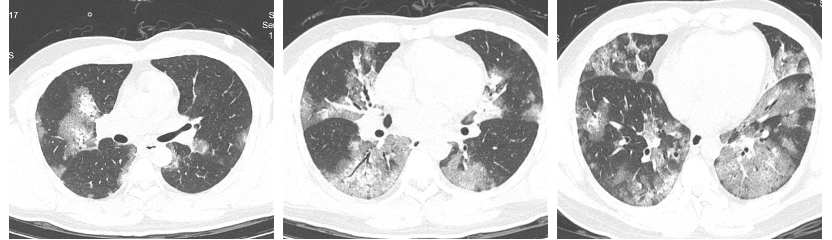

劉先生的兩肺都有非常嚴(yán)重的磨玻璃樣滲出,也就是平時(shí)所說(shuō)的“白肺”。

醫(yī)院供圖 治療前胸部CT(兩肺彌漫性磨玻璃樣滲出)

在醫(yī)護(hù)人員的努力下,劉先生的病情逐漸穩(wěn)定,高燒逐漸消退,胸悶氣急的癥狀也得到了緩解。再次復(fù)查胸部CT,兩肺的炎性滲出都有不同程度的吸收。經(jīng)過(guò)這次大病,劉先生感覺(jué)重獲新生。